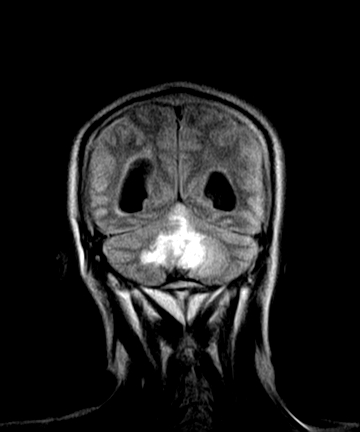

标题: MRI2064:少见病例。男性52,视力下降多年。 [打印本页]

标题: MRI2064:少见病例。男性52,视力下降多年。

四脑室区见混杂信号占位影,脑室系统扩张明显,临近结构显著受压称位,患者52岁,多考虑室管膜瘤可能性大

考虑第四脑室室管膜瘤并阻塞性脑积水。

考虑第四脑室室管膜瘤并梗阻性脑积水;部分性空蝶鞍;左侧上颌窦粘膜下囊肿。

考虑第四脑室室管膜瘤【血供丰富血管母细胞瘤可能】并梗阻性脑积水;部分性空蝶鞍;左侧上颌窦粘膜下囊肿。

比较典型的脉络丛乳头状瘤并脑积水,鉴别小脑蚓部血管母细胞瘤。